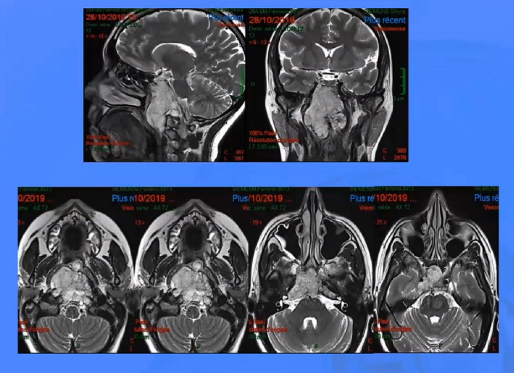

▼下图所示案例肿瘤看着很大,然后用30度、45度甚至70度的内镜,我们有很多带角度的器械,利用这些器械就可以切除肿瘤。可以先切开黏膜,然后把蝶窦内的黏膜推开,然后进入肿瘤。目前我们正在努力的开发这方面的器械,没有这些器械我们是做不了手术的。

▼下面就是我所说的有角度的器械,最后我们用脂肪来修补,我们在内镜下做缝合,在内镜下做缝合很复杂难度很大,所以很花时间,但是它是值得的。

▼这是术后的MRI,大家看到的高信号的是脂肪组织,我觉得利用内镜到达颅颈交界区更简单。